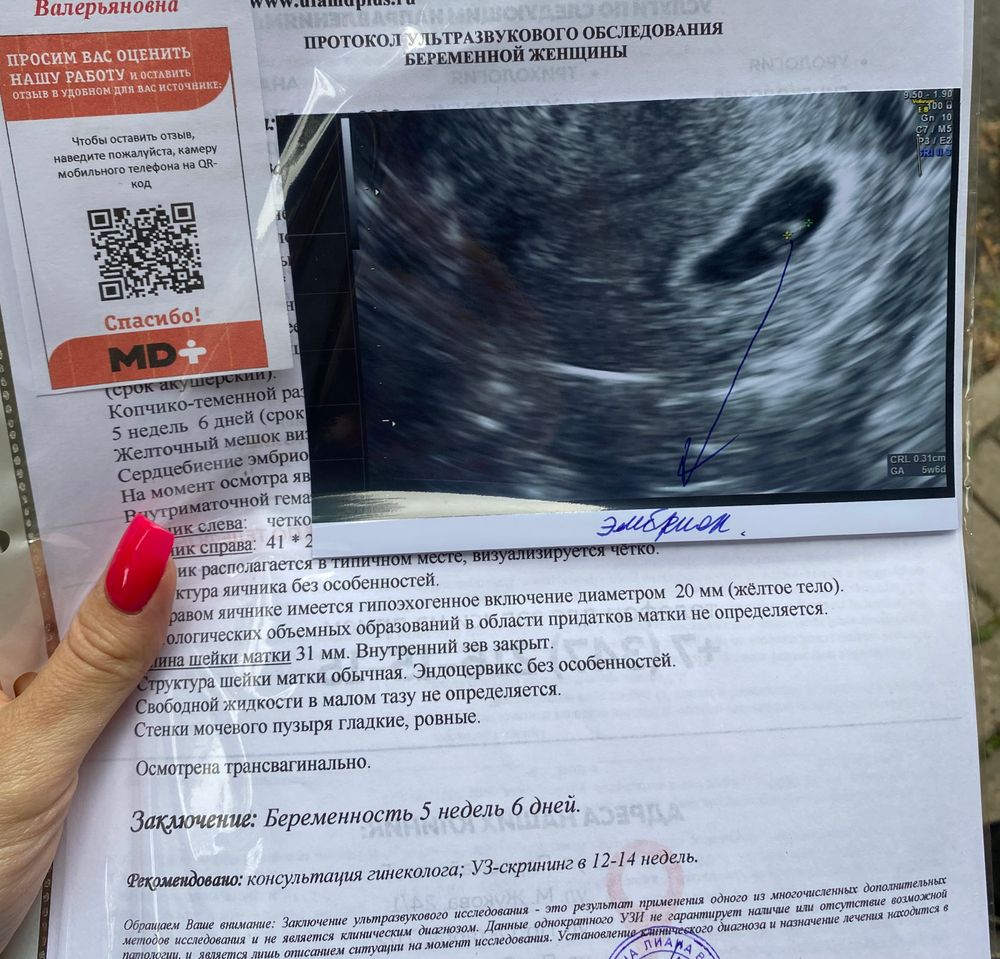

УЗИ, КТГ, доплерИтак, у меня сегодня 5 недель и 6 дней) Сегодня первое узи😍 Увидела уже нашего малышика) посетила женскую консультацию, на учёт не поставили, но взяли соскоб ШМ и направили на анализы 13 числа) токсикоза нет вообще, но жкт что то вредничает

вот результаты узи

Настёна, не знаю 🤷🏻♀️ У меня 3 разных срока стоит в заключении узи, посмотрите пожалуйста: по месячным 7 недель и 6 дней, по плодному яйцу 6 недель и 6 дней, а по размеру эмбриона 5 недель и 6 дней 🙄🙄🙄 Но знаю что овуляция была 8 июня +1-2 дня)

Настёна, привет!) меня пучит тоже дико, особенно к вечеру, там вообще как на 6 месяце хожу 🥲 я вот удивилась что у меня на сроке 5+6 уже увидели эмбрион и даже сердцебиение 😨 Боли в животе есть какие нибудь у вас? У меня иногда бывает ощущение, что матка очень напряжена((